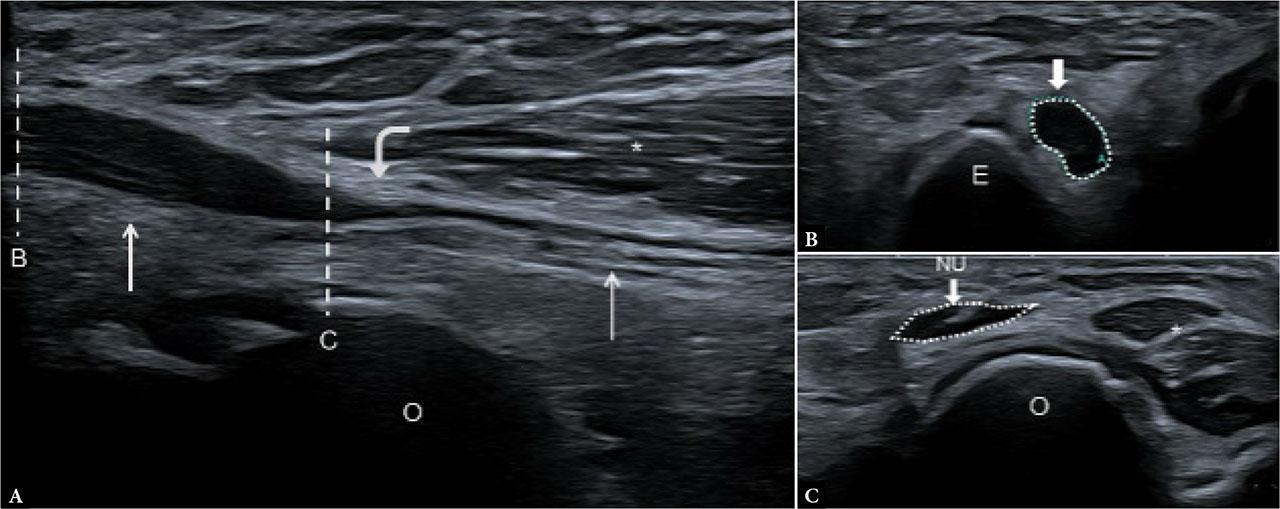

Presence of fibrous septa or aponeurotic bands arising from the flexor–pronator origin (Fig. 3) and post-traumatic fibrosis or scarring, can alter the normal gliding environment of the ulnar nerve and predispose it to entrapment.

Ulnar nerve impingement at the FCU level. Ultrasound with longitudinal (A) and axial (B, C) views with corresponding levels (dashed lines). The ulnar nerve (straight arrows) appears hypoechoic, enlarged, and swollen (B) proximal to the FCU arcade (curved arrow). At the FCU level, the nerve appears flattened (C) with intraneural hyperechoic spot due to possible fibrosis. Distal to the compression site, the fascicular pattern is preserved in (A). (NU and dotted circle) ulnar nerve; (E) epicondyle; (O) olecranon; (*) FCU muscle

Ultrasound findings. Enlargement of the ulnar nerve cross-sectional area (CSA) distal to the tunnel may suggest continued compression. Fascial fibrous hypertrophy between the heads of the FCU can be seen. Color Doppler imaging may show hyperemia in inflammatory causes. Anomalous accessory muscles (e.g., accessory palmaris longus, accessory flexor carpi ulnaris, or accessory abductor digiti minimi) have been reported as potential causes of ulnar nerve compression and should be considered when evaluating more distal sites in the forearm(21), although a precise description of these entities lies beyond the scope of the present article.